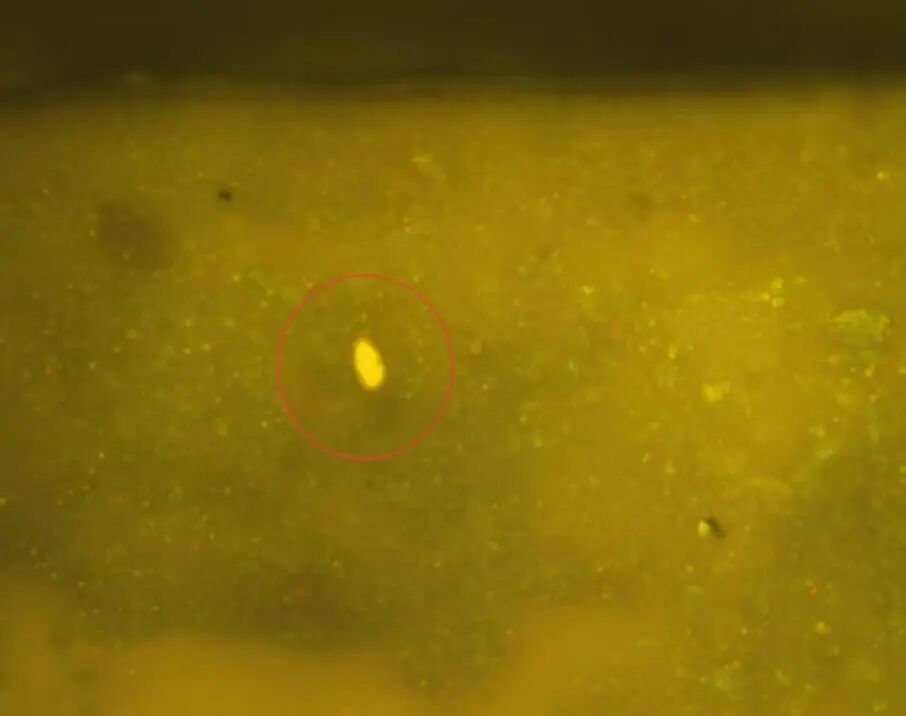

显微镜下观察到的肝吸虫卵

粪便中也直接检出了肝吸虫卵